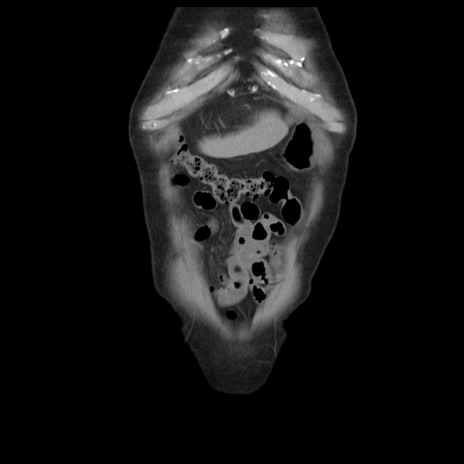

横断像